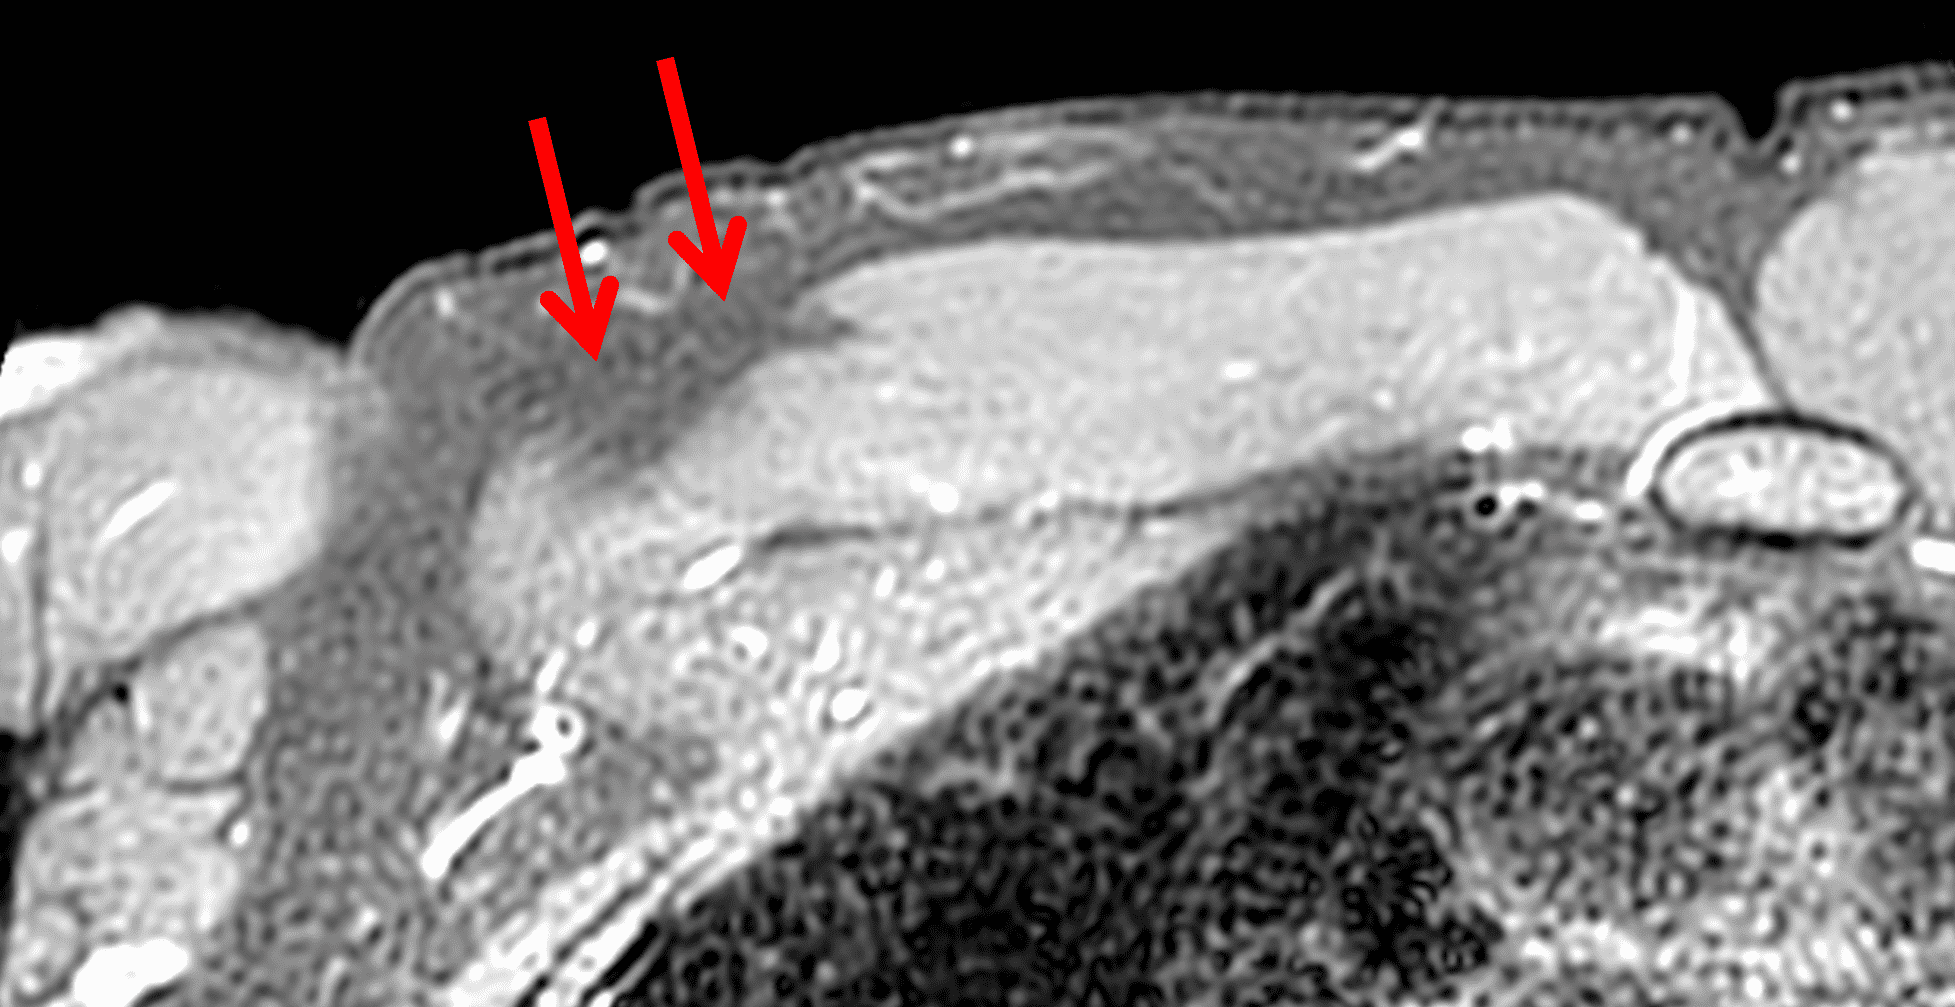

Primary imaging signs of PM injury include absence of the tendon at the humeral attachment (Figure 2B), tendon laxity, direct visualization of gaps in the tendon or a retracted tendon stump (Figures 2A and 8A). Of the primary signs, Baker et al. found lack of tendon visualization was the most accurate in isolation.19 The normal PM tendon should be visible on multiple continuous axial images through the proximal humeral shaft (Figure 10).

Secondary signs include hematoma, edema contacting the anterior humeral surface and anterior displacement of the long head of biceps tendon (LHBT) due to loss of the overlying retinacular function of the torn PM tendon (Figure 8A).15,19 In a series of 26 subjects, Godoy et al. found LHBT displacement of 4.5 mm or greater from the floor of the bicipital groove provided 86% sensitivity and 75% specificity for complete, 2-layer PM tendon tears from the humeral attachment.15 Baker et al, found edema contacting the anterior margin of the humerus helped improve radiologist’s ability to accurately distinguish tendon avulsions from MT injuries in the acute or subacute setting.19 Occasionally, if a PM injuries is unsuspected clinically, a shoulder joint MRI may be requested rather than a chest wall examination. Subtle findings suggesting a PM injury may be visible on shoulder images. The “smoke sign” was recently proposed to help identify PM injuries – especially humeral avulsions – in this scenario.20 The appearance of smoke billowing from a distant horizon is created by edema lateral (on coronal images) and anterior (on sagittal and axial images) to the short head biceps and coracobrachialis, with a relatively sharp margin (Figure 11). The sharp demarcation provided by these tendons constitutes the horizon of the smoke sign. The sign is not intended to be used as a method of distinguishing between humeral attachment and MT injuries. Of the group of 38 test subjects, the smoke sign was present in 24/24 humeral avulsions, 4/4 intratendinous injuries, 4/8 MT injuries and 0/2 intramuscular injuries.20

Figure 11: “Smoke sign” as a clue to a pectoralis major injury on shoulder MRI. (11A) Axial T2-weighted image from a shoulder MRI does not extend distally to include the pectoralis major tendon but shows edema along the anterior margin of the coracobrachialis muscle (arrows), the “smoke sign.” (11B) Sagittal T2-weighted image from a shoulder MRI shows a sharp posterior margin of the edema along the muscles (arrows). CB/B = coracobrachialis/short head biceps muscle bellies. (11C) Because of the findings on the shoulder images, the patient returned two days later for a dedicated chest wall MRI, with a fat-suppressed axial T2-weighted image from that study confirming a completely torn, retracted pectoralis major tendon (arrow).